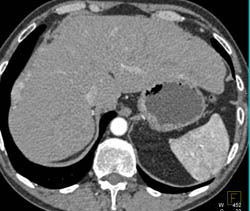

Diagnosis

Hepatoma